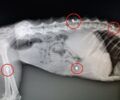

Η Πανελλαδική Φιλοζωική και Περιβαλλοντική Ομοσπονδία (Π.Φ.Π.Ο.) επιδιώκοντας να βάλει ένα τέλος στο εμπόριο ζώων μέσω καταστημάτων συγκεντρώνει στοιχεία, που αποδεικνύουν, το τι τελικά υφίστανται αυτά τα πλάσματα που πωλούνται ως προϊόντα μέσα στα pet shops. Αν αγοράσατε ζωάκι το οποίο δεν φέρει μικροτσίπ, όπως ορίζει ο νόμος 4039/2012, αν δεν συνοδεύεται από βιβλιάριο υγείας, αν είναι ανεμβολίαστο κ.ο.κ. στείλτε επώνυμα τις καταγγελίες σας στο email της Π.Φ.Π.Ο. [email protected].